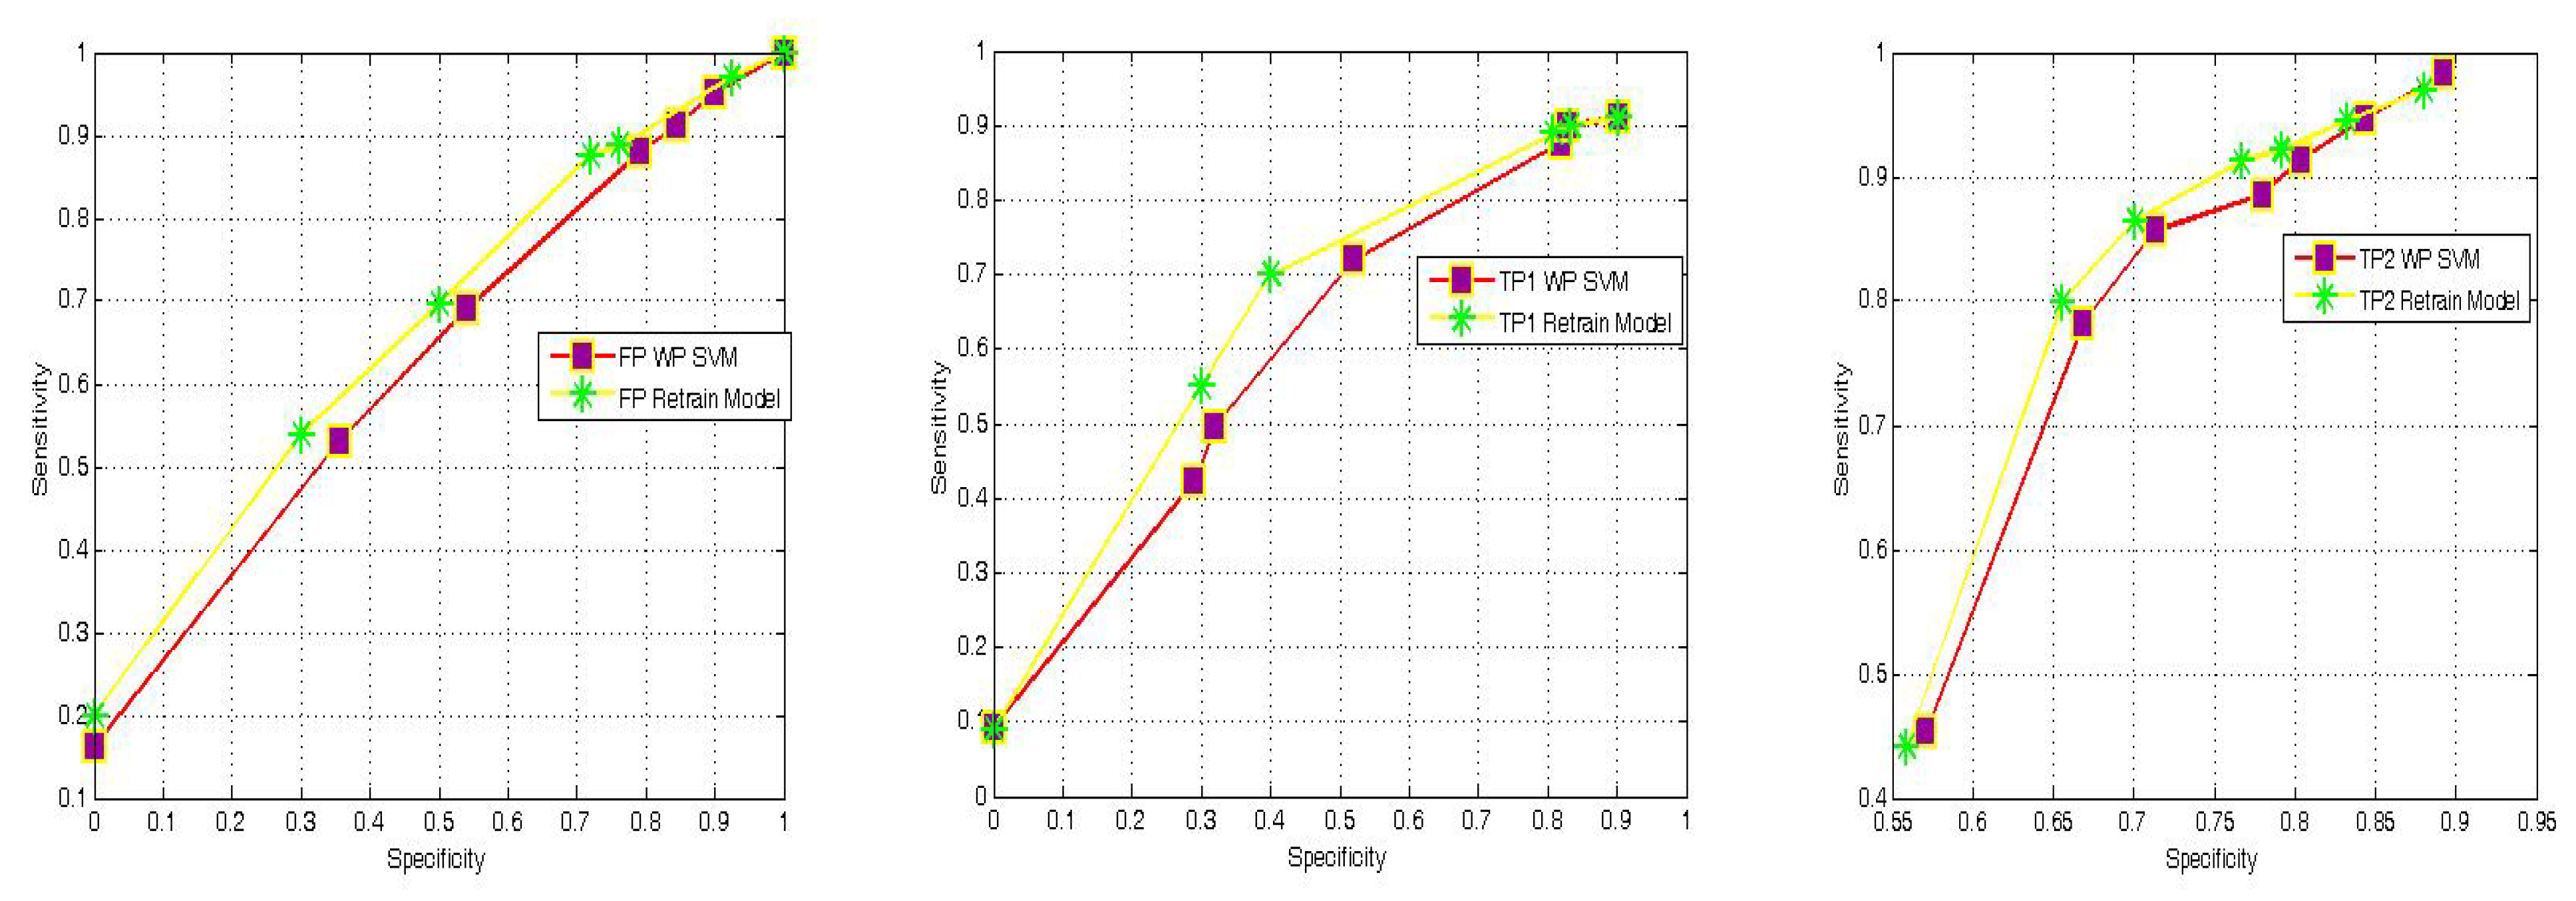

3.1. Proposed Multi-Classification

| Matrix Symbol | Matrix Element |

| C | Diagonal matrix of size (f*c) by (f*c), the diagonal elements are composed of the square matrix cn which is of size f: |

| D | Diagonal matrix of size (f*c) by c, the diagonal elements are the column vector dn of length f |

| E | Column vector of size c made from |

| H | Matrix of size (f*c) by c. The row vector is hn of length c and of the form |

| G | Square matrix of size (f*c) by (f*c), composed of matrix gn of size f by c such that |

| Q | Square matrix of size c, made from the row vector qn of length c qn = [(q(1)+q(n)) ... (q(c)+q(n))] |

| U | Column vector of size c, made from un such that un = −2(N −cq(n)) |

| R | Square diagonal matrix of size c, the diagonal elements rn are as follows |